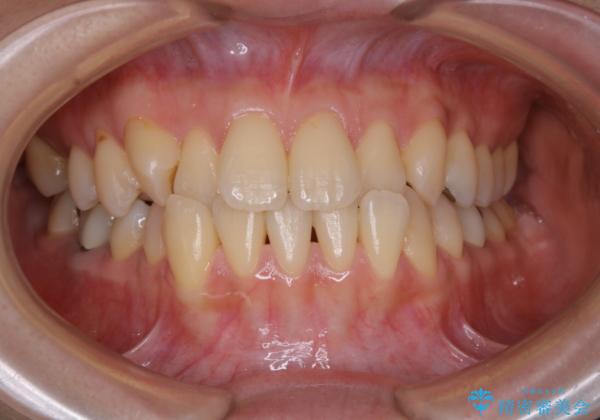

前歯が内側に入っている:インビザライン治療

- 上の前歯は内側に入っていることが気になりご相談にいらした方です。インビザラインにて治療を行いました。

1週間でのマウスピース交換を指示していましたが、20時間以上使えない時があると不安との事で、2週間ごとの交換にしていました(実際はほとんど20時間以上使用できていたようです)。治療終了まで時間はかかりましたが、最終的に綺麗に並べることができ、大変喜んでいただけました。